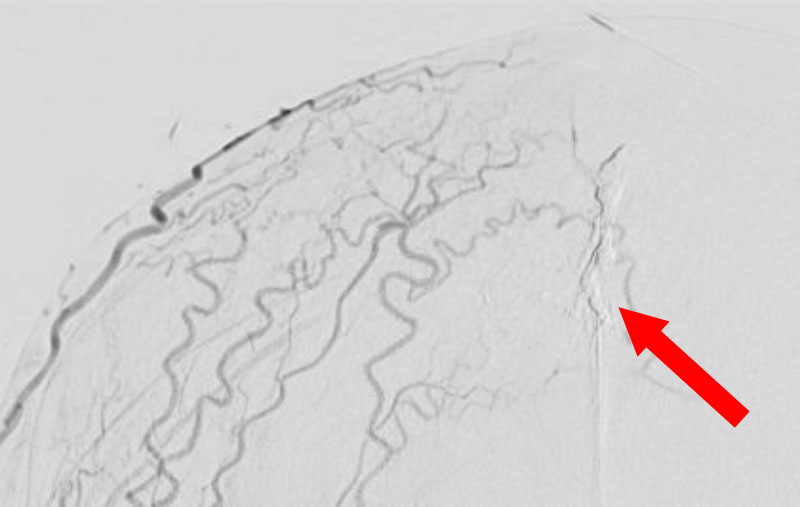

1615

'26年2月21日

硬膜動静脈瘻

50代

大阪府の病院

中

治療